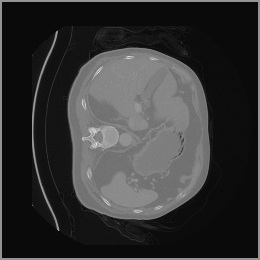

The motivation for this work arises from the need to address these limitations in the synthesis of 3D medical images. Current techniques do not produce high-resolution 3D images that preserve spatial coherence and capture the full complexity of medical data, as shown in Figure 2, 5. The development of advanced 3D generative models tailored specifically for medical imaging could not only improve the quality of synthetic medical images but also help alleviate data scarcity, enhance privacy protection, reduce computational requirement and ultimately advance the use of deep learning in healthcare applications.

To demonstrate the advantages of 3D semantic image synthesis over 2D semantic semantic image synthesis, we conducted a detailed comparison with the SegGuidedDiff [26] model. SegGuidedDiff generates medical images based on 2D semantic maps, producing individual 2D slices that are later stacked to form a 3D image. However, this approach has limitations in capturing spatial continuity and coherence across slices, which is critical for representing the spatial structure of 3D medical images. As a result, inconsistencies often arise between different slices, particularly in preserving anatomical structures across the coronal and sagittal planes. The generated images exhibit varying levels of denoising, resulting in differences in brightness and sharpness across the images. This inconsistency in denoising can lead to noticeable variations in visual quality, where some regions appear clearer and others less distinct.

As shown in Figure 5, the generated slices exhibit high consistency across adjacent slices. The anatomical structures and semantic patterns are smoothly and coherently preserved between slices, indicating that our model is capable of generating 3D-consistent synthetic images rather than isolated 2D slices.